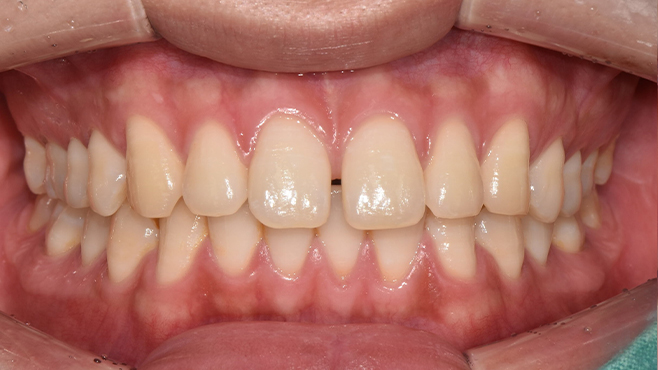

맞는 건 괜찮은데… 충치는 못 참겠습니다|20대 격투기 선수 치과 방문기